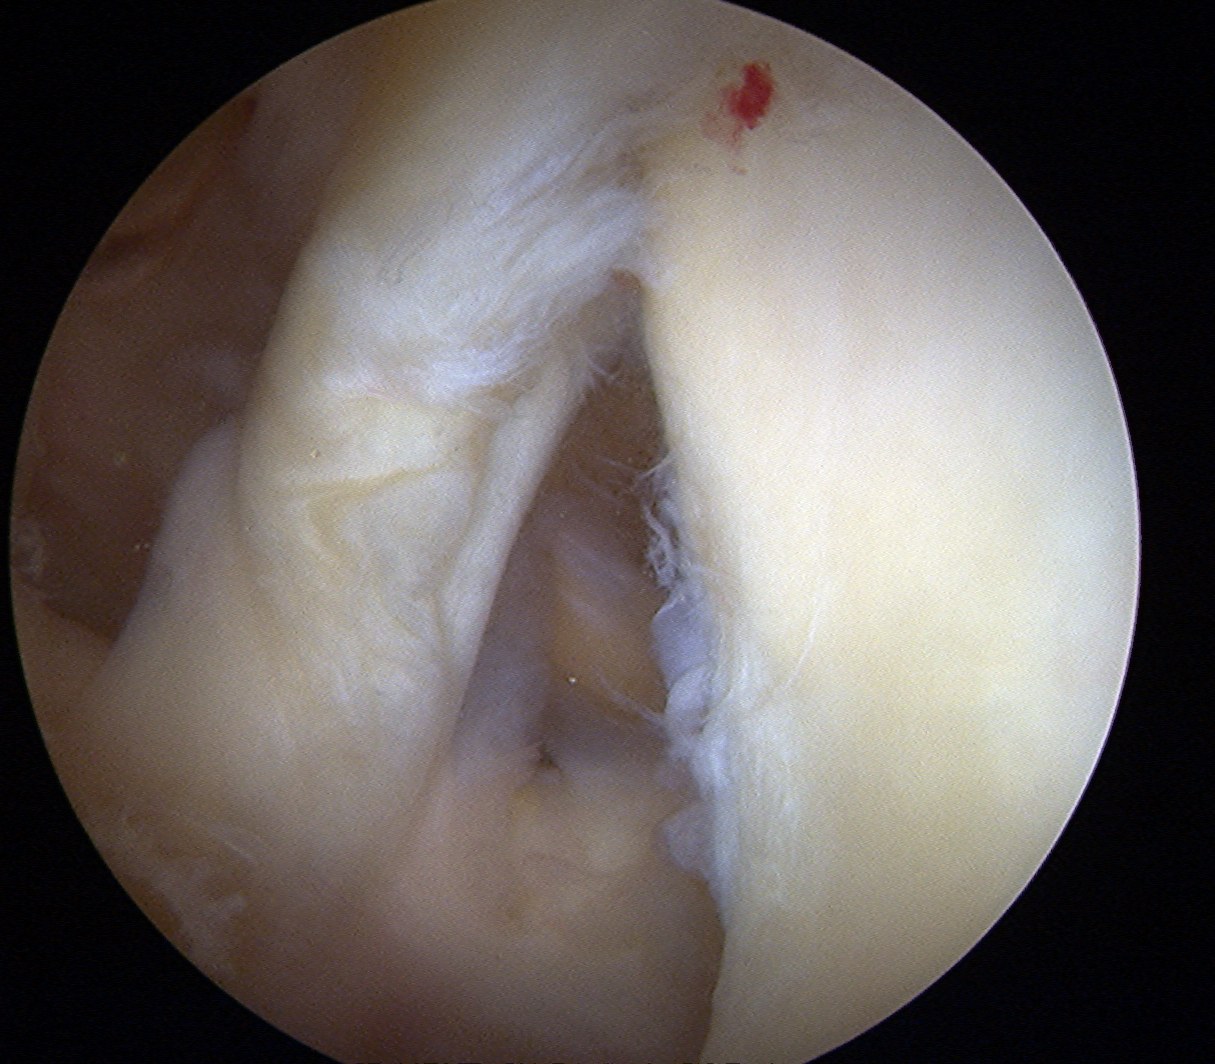

Labrum

Anterior inferior labral tears |

SLAP tears | Posterior labral tears |

Below equator 3 - 6 o'clock |

Mobilize labrum

Labral mobiliser / rasp

- labral tear can be obvious, but may have partially healed or healed medially

- change camera to anterosuperior portal for better view

- mobilize until can see subscapularis muscle underneath

- need to be able to advance labrum medially and superiorly for repair